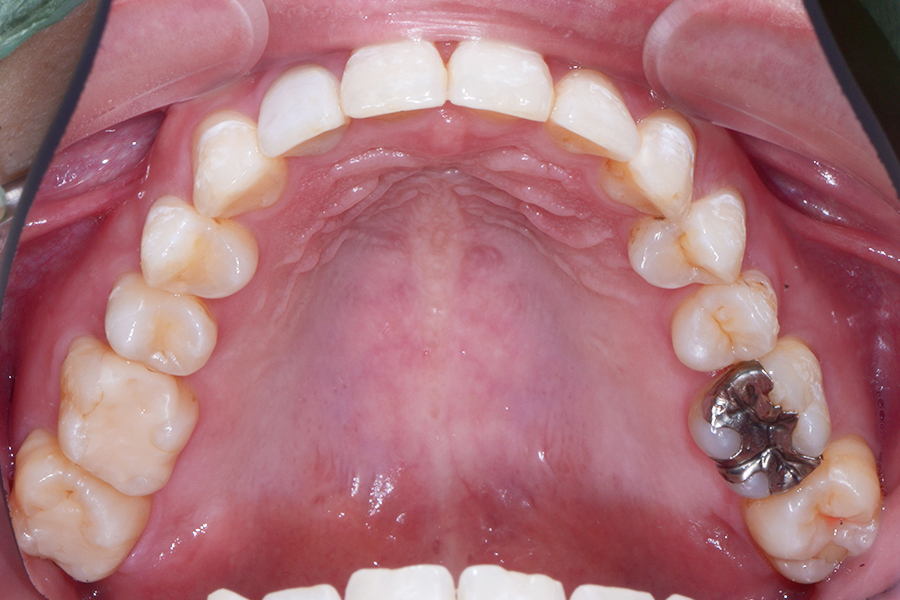

【20代女性】すきっ歯(隙間)と

咬み合わせを良くしたい

【矯正歯科治療】

- 担当医

- 三留先生

- 主訴

- すきっ歯(隙間)と咬み合わせを良くしたい

- 期間

- 治療期間10か月

- 費用

- 治療費35万+20万(別途調整料)

- 治療内容

- ハーフリンガル矯正(上顎裏側・下顎表側矯正)

- 治療に伴うリスク

- 後戻り